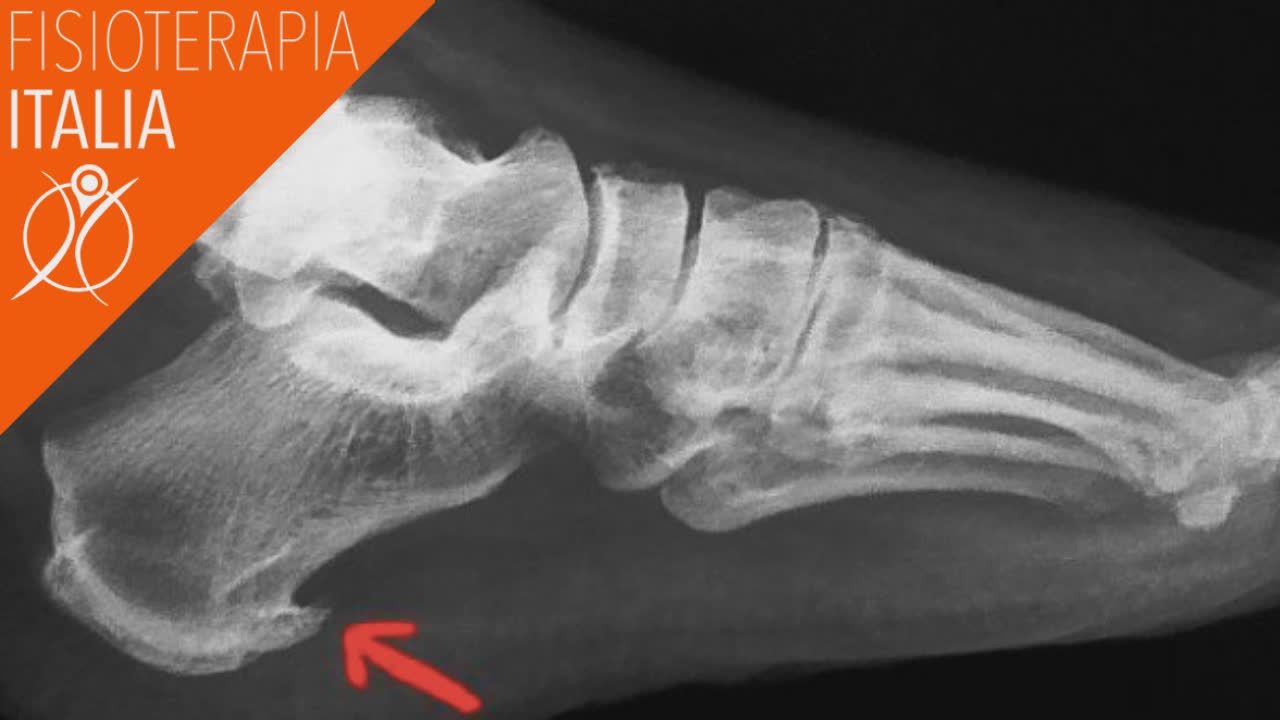

Tallonite cause e rimedi

Tallonite cause e rimedi from www.fisioterapiaitalia.com